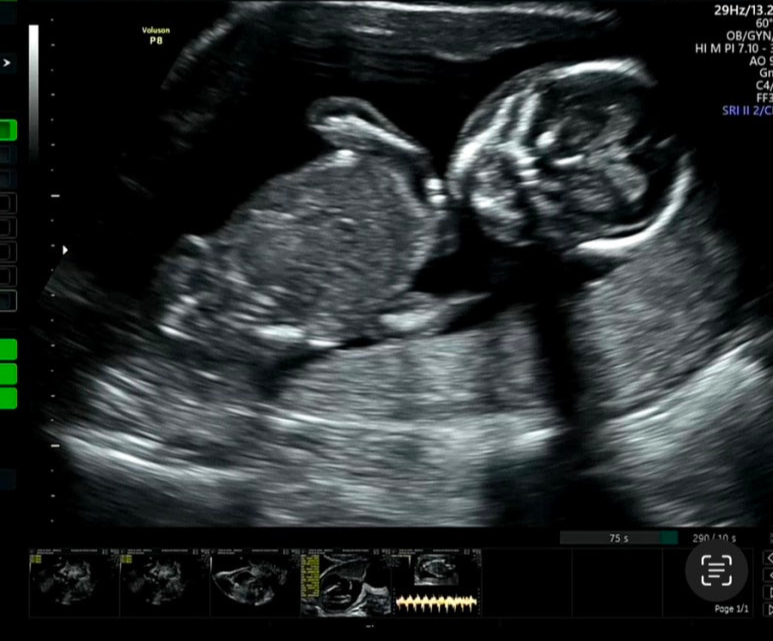

드뎌 한달만에 만난 우리애기이이

그새 무럭무럭 자랐네 흐미

지난번이랑 또 다른 디테일들이 생겼다 요목조목

초음파 하는 내내 꼼지락 꼼지락 대는게 귀엽다

ㅋㅋㅋㅋㅋㅋㅋㅋㅋㅋㅋㅋ너무 신기해

심장도 우렁차게 쿵캉쿵캉 뛰고

꼼지락 꼼지락 손을 입에도 가져다 대기도 하고

진짜 너무 기엽네 ㅠㅠ 참나

갈비뼈도 좌라라락 보이는게 제법 많이 컸어 정말

손가락도 뼈다귀가 신기하게 다 보이고.

야무진 엉덩이 좀 바여 아이구 미치겠네

ㅋㅋㅋㅋ 귀여워라